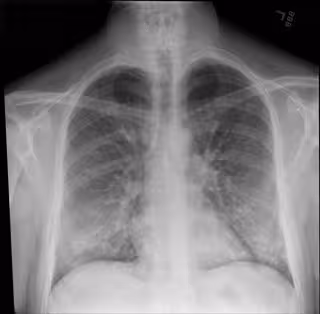

Radiografía de tórax de un paciente que está siendo tratado por una lesión pulmonar asociada a vapeo o cigarrillo electrónico.

Radiografía de tórax de un paciente que está siendo tratado por una lesión pulmonar asociada a vapeo o cigarrillo electrónico. - INTERMOUNTAIN HEALTHCARE

El diagnóstico se definió por un historial de vapeo o uso de cigarrillos electrónicos dentro de 90 días antes de los síntomas, anomalías que se muestran en las imágenes de tórax y ninguna otra causa de estos hallazgos (como la neumonía).